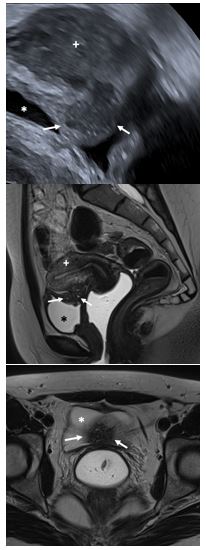

Fig 1 Adénomyose antérieure

• Echographie endovaginale, coupe sagittale passant par l’utérus

• IRM coupe sagittale T2 passant par l’utérus

Adénomyose interne diffuse du mur antérieur (*)

Fig 3 Nodule digestif

• Echographie endovaginale Coupe sagittale passant par la paroi antérieure de la jonctionrecto-sigmoïdienne

• IRM coupe sagittale T2 passant par la vessie et l’utérus

• IRM Coupe axiale T2 passant par l’utérus et les ovaires

Nodule d’endométriose digestive transmurale (*) de la jonction recto-sigmoïdienne

Fig 4 Endométriose de vessie

• Echographie endovaginale Coupe sagittale passant par la vessie et l’utérus

• IRM Coupe axiale T2 passant par le nodule de vessie et la vessie

Nodule d’endométriose vésicale (flèches), vessie (*), utérus (+)